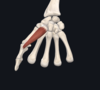

- extensor digiti minimi

- lateral epicondyle; extensor hood of little finger (along with extensor digitorum)

- radial nerve

- extends little finger (also contributes to extension at wrist)